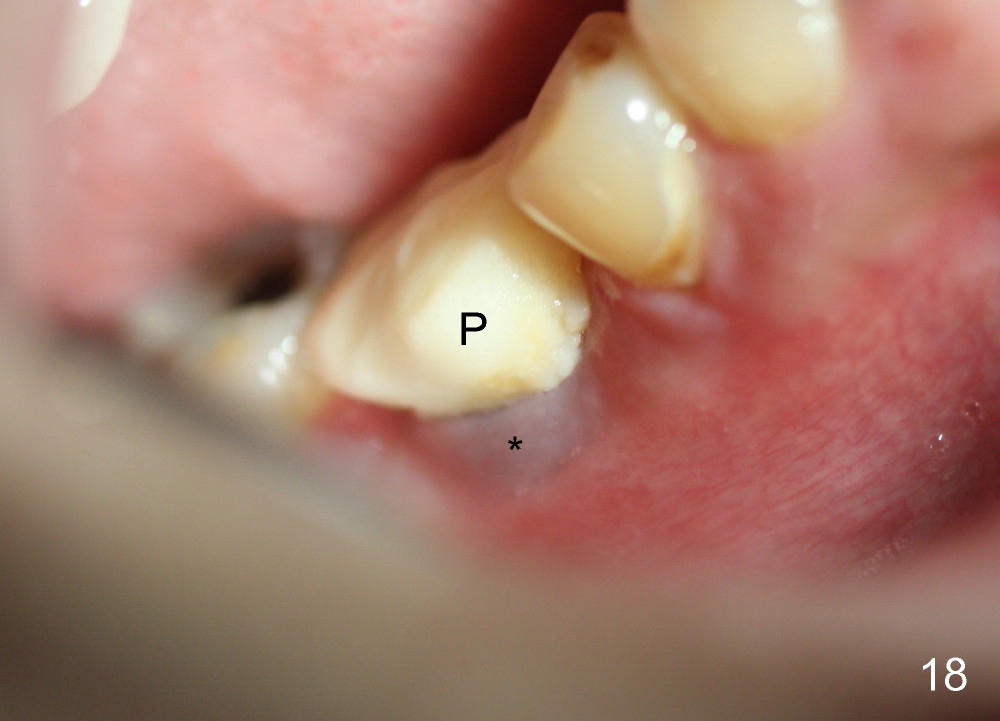

A 38-year-old lady agrees to have implant placement 7 years after loss of the crown of the lower right first molar (Fig.1,2). When the tooth is extracted, the septum is found to be low (Fig.3,4). To confirm it, a PA is taken (Fig.5). To initiate an osteotomy in the septum, it is trans-sectioned with thin osteotomes as shown in Fig.4 insert (black line). A 2 mm pilot drill is placed in the septum (Fig.6: P). The osteotomy is enlarged by 2.5-4.0 mm reamers (Fig.7,8), followed by insertion of 6x17 mm tapered tap at the depth 14 mm (Fig.9). The osteotomy is further enlarged by 4.5 and 5.0 mm reamers. A 6.0x14 mm one piece implant is placed initially. The trajectory is not ideal. A 6.0x14 mm one piece implant is placed initially. The trajectory is not ideal. The implant is removed from the osteotomy partially and reinserted with improved trajectory (Fig.11, compare to Fig.10 (red line)). Primary stability is high. There is not much bone mesiodistally so that the trajectory is easily changed in that direction. After abutment preparation, mixture of autogenous bone (harvested from reamers) and allograft is placed in the residual mesial and distal sockets (Fig.12). To contain the bone graft, an immediate provisional is placed (Fig.13 P). The occlusal plane of the provisional is significantly lower than that of the adjacent teeth to avoid micromovement of the implant. The patient is advised to eat soft food on the left side. Six days postop, the patient returns for prophy. The provisional is removed; the bone graft appears to be incorporating into the socket (Fig.14). After recementation, the provisional remains in place for 3.5 months; PA shows increased bone density in the mesial and distal sockets (Fig.15, compare to Fig.5,11). Due to insurance coverage, the patient defers fabrication of definitive restoration for at least 7 months. The immediate provisional is finally lost 8.5 months postop: the gingiva attaches to the 1-piece implant (Fig.16), while the density of the mesial socket increases (Fig.17 *) with formation of the cortex (lamina dura) coronally (v). Before the provisional (Fig.18 P) is removed for cementation of the definitive restoration, black shadow (*) is noted over the buccal gingiva. It is partially due to buccal placement (Fig.19) and partially due to buccal atrophy over a period of 10.5 months postop. How to prevent buccal placement? Positioning the first pilot drill in the septum buccolingually is a key. Eleven months post crown (Fig.20 C) cementation, the black shadow remains, but there is no tenderness. If the implant threads are immediately underneath the periosteum, there is tenderness.